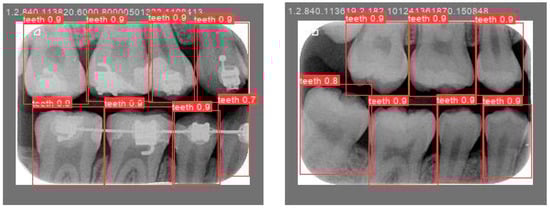

The validation results are shown in Figure 12. The accuracy of the judgment of a single tooth in each BW image is within the range of 80% to 90%. This high level of accuracy demonstrates that automated tools can be trusted to process large volumes of image data without requiring extensive time for individually marking the position of each tooth. Furthermore, we compared the YOLO-based method and the rotation-aware single-tooth segmentation algorithm developed in this study. As shown in Table 5, the segmentation average accuracy (ACC) of YOLOv8 is comparable to that of our proposed algorithm. However, the proposed method demonstrates a faster inference time (IT) for individual tooth segmentation and effectively addresses errors caused by variations in image tilt angles. A paired t-test was performed between YOLO and the proposed model on 40 validation images. The p-value of 0.013 indicates a meaningful and statistically supported improvement in performance. The paired t-test is shown in (5), where Xi and Yi represent the two Intersection over Union (IoU) values of the i-th paired data. The difference di is calculated by subtracting Yi from Xi, and N denotes the total number of paired samples.

Figure 12.

Validation results.